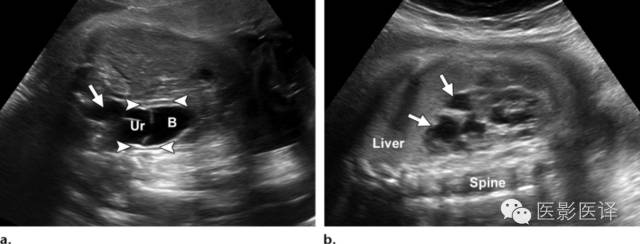

输尿管囊肿

输尿管囊肿是由于输尿管末端扩张而形成。超声表现为位于膀胱内的薄壁、无回声囊性肿块,偶尔会形成假分隔。影像上,如果能看到该囊性肿块是输尿管的直接延伸即可确诊输尿管囊肿(图11)。输尿管囊肿可分为单纯性和异位性。单纯性输尿管囊肿位于膀胱输尿管入口处(膀胱三角区)。异位输尿管囊肿通常与肾脏集合系统重复畸形相关,肾脏上半部分的输尿管插入点位于膀胱三角区的内下方。单纯性或异位性输尿管囊肿可能导致输尿管积水及肾盂积水。巨大的单纯性输尿管囊肿可能会阻塞对侧输尿管口,异位性输尿管囊肿可能导致重复集合系统的输尿管口狭窄。通常,肾盂积水是常规超声检查最早发现的。膀胱部分充盈是诊断输尿管囊肿的理想状态,因为膀胱完全充盈时可能压迫输尿管囊肿,而膀胱不充盈时可能将输尿管囊肿误诊为膀胱本身。一旦诊断了输尿管囊肿,还应仔细检查整个泌尿生殖道,排除是否合并集合系统畸形(图12)。

因为尿液是无回声的,一个内部有回声的肿块不应该被误诊为输尿管囊肿。少数输尿管囊肿位于膀胱外,可能会与腹内其他囊肿相混淆,包括那些卵巢来源的。一般而言,输尿管囊肿是在膀胱内而不是与膀胱相邻,它的大小会随尿流量而变化。然而,卵巢囊肿大小不会变化,通常位于膀胱的旁矢状面上方。

图11.输尿管囊肿及输尿管积水。(a)通过胎儿盆腔的超声斜横断面图像显示膀胱(B)内由输尿管囊肿(Ur)引起的“膀胱内膀胱”的征象。注意由此引起的输尿管积水(箭)。箭头指示脐动脉绕过膀胱,(b)同一胎儿,通过右肾的超声冠状面图像显示明显的肾盏扩张(箭)和被阻塞的上半部分肾皮质变薄。